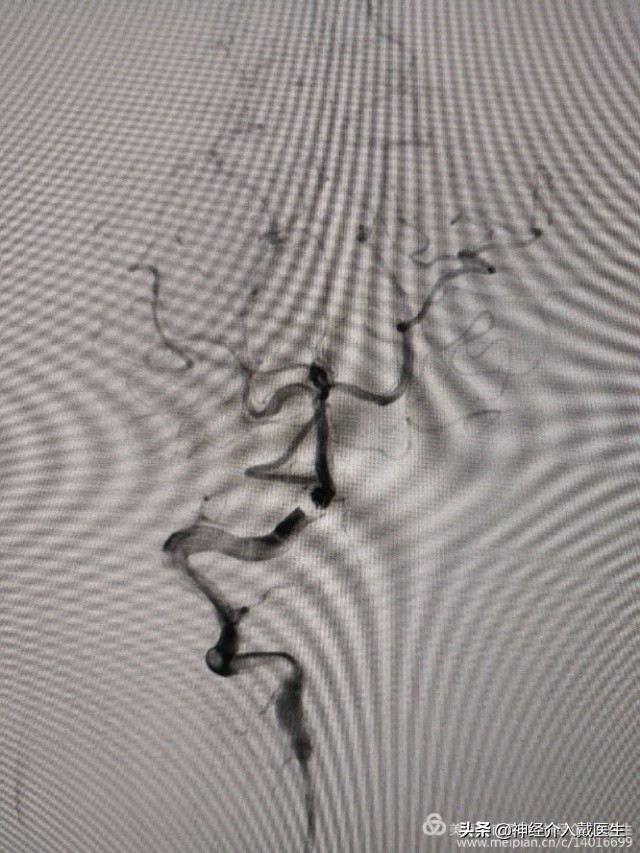

通过真腔放置支架导管,放置弹簧圈导管,释放一个5mm*12cm弹簧圈后,考虑需要保护小脑后下动脉,支架网孔大小很重要,我们选择Enterprise2支架,4mm*23mm一枚,

依次释放6mm*9cm,4mm*8cm,2mm*2cm,2mm*2cm弹簧圈各一枚,造影显示动脉瘤腔致密栓塞。

复查椎动脉正位,动脉瘤不显影,载瘤动脉及右侧小脑后下动脉通畅。

复查椎动脉侧位,动脉瘤不显影,载瘤动脉及右侧小脑后下动脉通畅。遂结束手术。